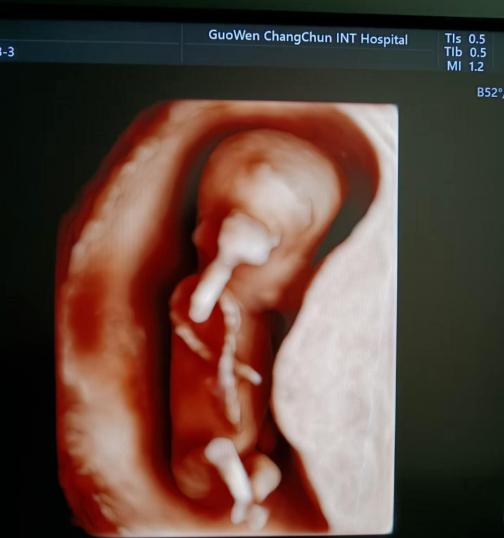

通常在懷孕 11 周 - 13 周 + 6 天之間進(jìn)行。這個(gè)時(shí)期胎兒大小適中,頸項(xiàng)透明層的顯示較為清晰,測量結(jié)果也相對(duì)準(zhǔn)確,能更好地發(fā)揮 NT 檢查對(duì)胎兒異常的篩查作用。

超聲檢查,孕婦無需空腹。檢查時(shí),超聲醫(yī)生會(huì)使用超聲儀器對(duì)胎兒頸部進(jìn)行仔細(xì)觀察和測量。通過超聲探頭可以清晰地看到胎兒在子宮內(nèi)的情況,重點(diǎn)測量胎兒頸項(xiàng)部皮下無回聲透明層最厚的部位,測量值即為 NT 值。正常胎兒 NT 值一般不超過 2.5mm。